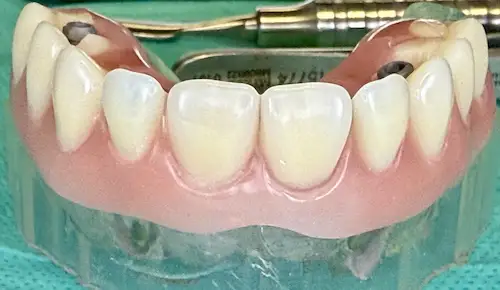

All-on-4 ® – Patientenfall

Bei Zahnlosigkeit oder nicht mehr erhaltungswürdigen Zähnen wünschen sich die Patient*innen der Praxisklinik Herne natürlich zeitnahe und minimalinvasive Lösungen. Dank des All-on-4 ® / All-on-6 ®–Konzepte können wir ihnen diesen Wunsch oftmals innerhalb nur eines einzigen Behandlungstages erfüllen: 4 bzw. 6 Zahnimplantate werden gesetzt und bilden im Folgenden die Grundlage für den passenden festsitzenden oder herausnehmbaren Zahnersatz. Die einzelnen Behandlungsschritte veranschaulichen wir Ihnen anhand eines aktuellen Patientenfalls aus diesem Jahr.

Der Patientenfall

Unser 55-jähriger Patient stellte sich uns nach Jahrzehnten der Nichtbehandlung mit einen stark kariösen und nur zum Teil bezahnten Kiefer vor. Aufgrund einiger abgebrochener Zahnwurzeln wurde schnell ersichtlich: Der bisherige Zahnersatz kann nicht erneuert werden; außerdem wünschte sich unser Patient in Zukunft einen gaumenfreien festsitzenden Zahnersatz. Alles deutete Richtung All-on-4 ® / All-on-6 ®–Konzept.

Patientenbild: Ober- und Unterkiefer vor der OP

Ermittlung des Status Quo und schrittweise Planung

Bevor an einen operativen Eingriff gedacht werden kann, stehen als erstes Röntgenbilder mithilfe der Digitalen Volumentomographie auf dem Programm. Hier sind die Überreste in Ober-und Unterkiefer gut zu sehen, vor allem aber die Positionen der abgebrochenen Zahnwurzeln. Auf Basis der Bilder können die Positionen für die insgesamt 8 Implantate auf den Millimeter genau geplant werden: Unser Patient wird jeweils 4 Implantate im Ober-und Unterkiefer erhalten, die im Nachgang jeweils mit einem festsitzenden Zahnersatz versorgt werden. Die Einheilphase dauert zwischen 4 und 6 Monate, prognostiziert Dr. Mintert, der Spezialist für Implantate in der ZPK Herne.